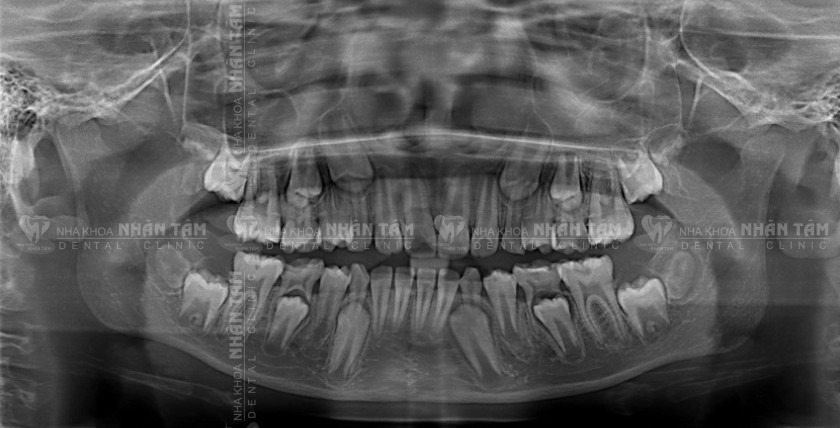

Chụp X-quang là một kỹ thuật chẩn đoán hình ảnh sử dụng tia X để ghi lại hình ảnh bên trong cơ thể. Trong nha khoa, chụp X-quang răng giúp bác sĩ nhìn thấy cấu trúc bên trong răng, xương hàm, và các mô mềm xung quanh, nhằm phát hiện những vấn đề không thể quan sát bằng mắt thường.

Chụp X-quang răng là một quy trình được sử dụng phổ biến trong nha khoa, giúp chẩn đoán các bệnh lý như sâu răng, viêm nướu, tiêu xương hàm, răng khôn mọc lệch, u nang, hoặc tình trạng răng trước khi niềng…